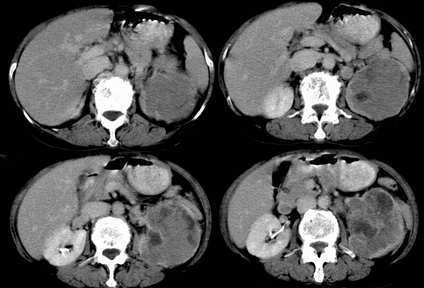

病患,女,69岁,左侧腰部不适,偶感疼痛2个月余,无化验室检查,行彩超发现左侧肾区实质性肿物,后行ct检查,结果同上。

左肾不规则软组织肿块,内见低密度坏死区,与正常肾实质分界不清,左肾明显增大,增强呈不规则条索状强化,肾盂及左输尿管上段扩张。肾周脂肪层受侵、模糊。印象:典型左肾癌。

平扫,表现为肾实质肿块,呈分叶状,肿块密度不均,内有不规则低密度区(陈旧性出血?坏死?)有的似呈囊性,增强明显不均一强化,与肾实质相比呈相对低密度的不均一肿块,肾周脂肪间隙可见,肾前筋膜未见增后,肾血管及腹主动脉旁未见肿大淋巴结影

左侧肾癌并肾静脉癌栓.腹膜后淋巴结肿大转移.

三期抓的不错,典型的肾癌,且已累及肾盂及左输尿管上段

左肾癌累及左输尿管,左肾静脉无受累征象。